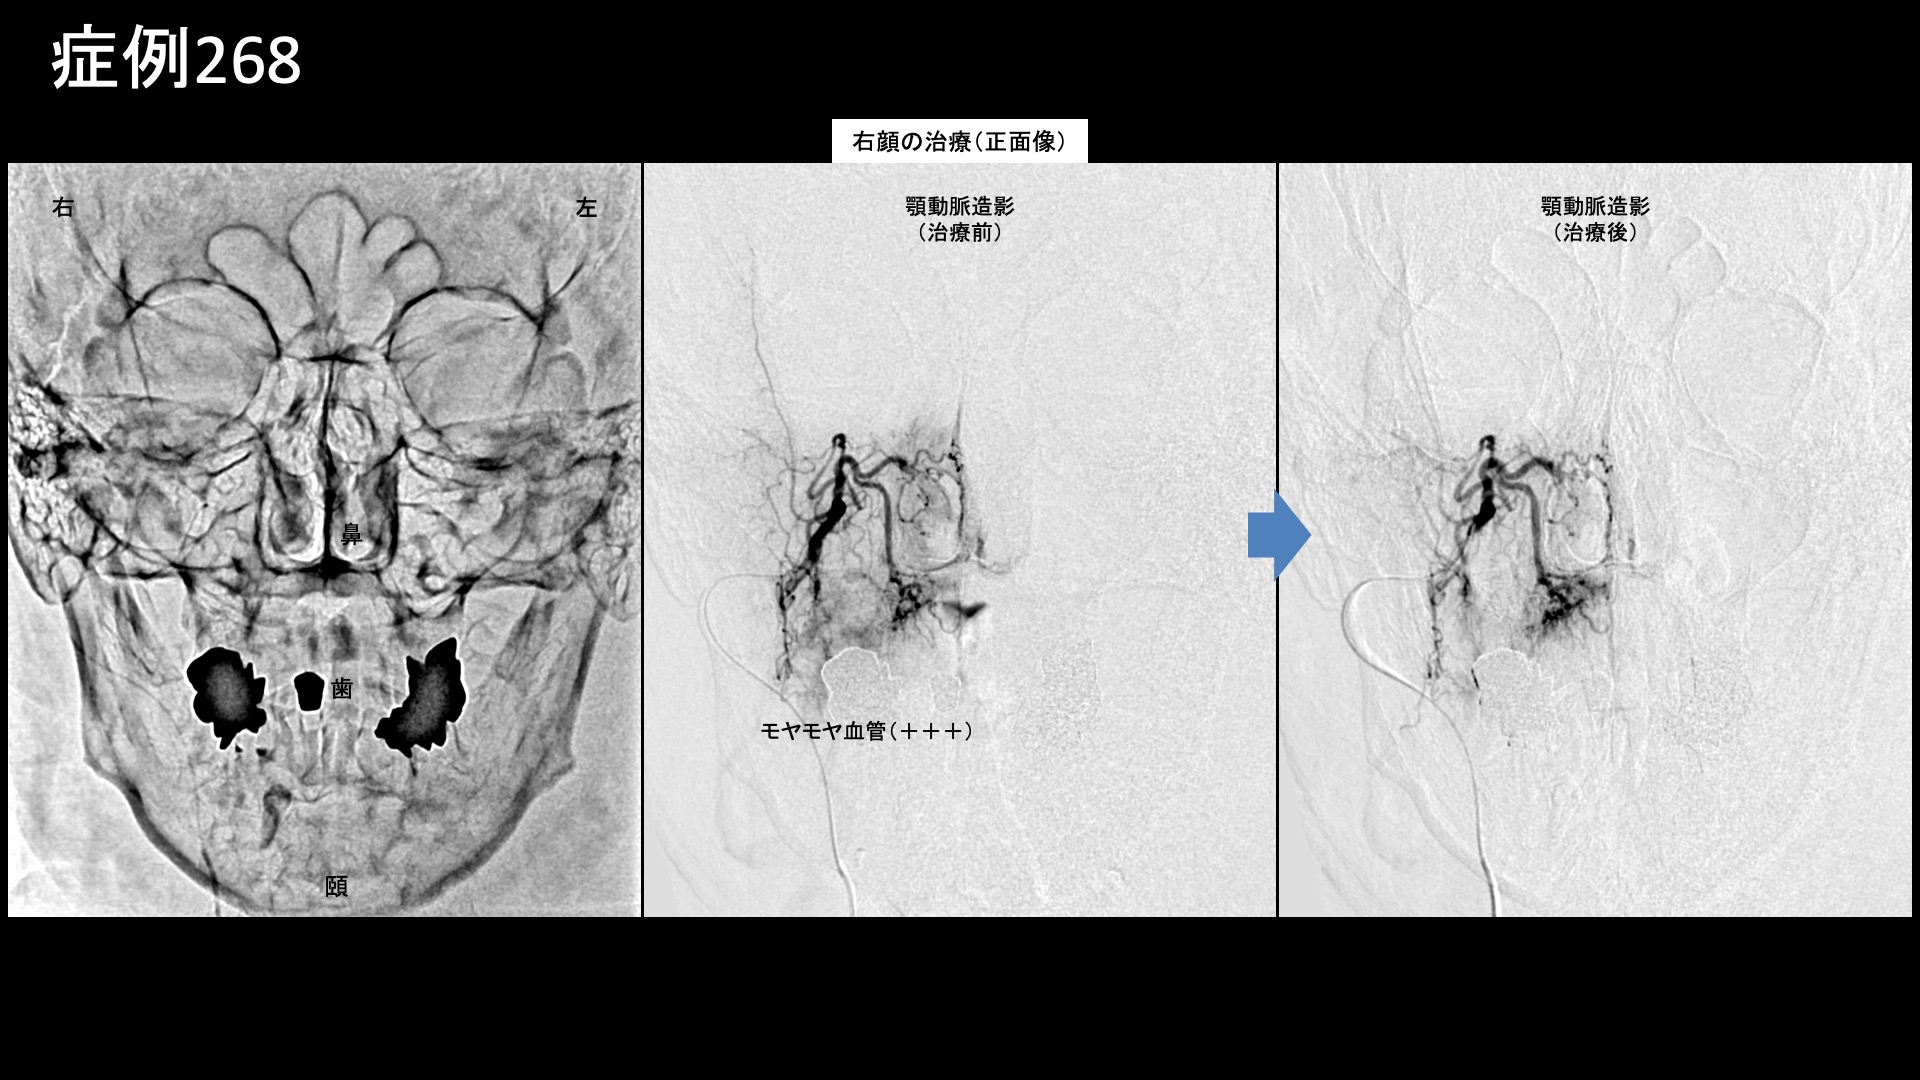

血管造影を行うと、顎動脈にてモヤモヤ血管が濃染像として描出されました。顎という名前が付いていますが、ここからはたくさんの血管が分枝しており、手前では下顎領域や歯、中間部では頬(頬筋)や咬筋・側頭筋など、遠位部では鼻腔や副鼻腔、歯や口蓋(いわゆる上あご)などに灌流します。出血部位の責任血管と考えられました。治療後モヤモヤ血管は画像上速やかに消失しました。再現痛も明瞭でした。頭部についてはモヤモヤ血管が強く描出されることは稀ですが、浅側頭動脈は血管全体が非常によく発達していました。炎症に伴い発達したものと捉えられます。その他複数箇所の治療を行い終了しました。

治療前画像:損傷を受ける、あるいは繰り返しのストレスにより発生した異常な新生血管

治療後画像:カテーテルを用いて塞栓物質を血管内に投与し新生血管を塞いだ状態